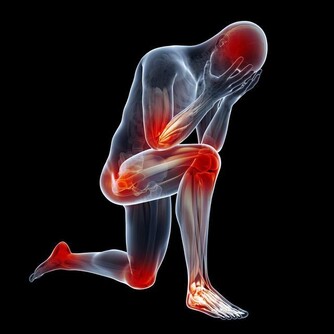

洋蔥辛辣,是一種熱性的食物,吃多了容易上火。陰虛的人身體虛弱,可能會承受不住洋蔥的熱,而導致一些不好的後果。而體熱的人,本身就容易上火或者是已經有點上火了,如果再吃了洋蔥,就更加加重了這種情況,這有可能會導致人出現發熱、長痘、喉嚨發炎等症狀。因此,這兩類人應該少吃一些洋蔥,並且避免食用其他熱性的食物,如煎炸的食物、荔枝、芒果等。